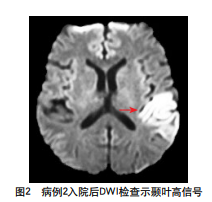

病例2

基本情况:36岁男性患者,无基础病史,因“突发双耳

临床表现:听理解差、言语不清,颈部抵抗,克氏征/布氏征(+);病程中出现右手持物不能、抽搐,反复发作。NIHSS 5分,FABS 5分,TM 7分。

辅助检查: